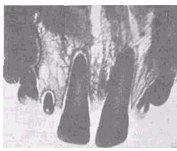

Очаговая одонтодисплазия описана в специальной литературе под разными названиями: фантомные зубы, незавершенный одонтогенез, одонтодисплазия. Это редкая патология, встречающаяся у практически здоровых детей.. Характеризуется запоздалым развитием и прорезыванием нескольких рядом расположенных зубов, как временных, так и сменяющих их постоянных, одного или разного периода развития. Чаще страдают резцы, клыки или постоянные моляры, реже — все зубы одной половины верхней челюсти. Коронки этих зубов уменьшены за счет недоразвития эмали, имеют желтоватую окраску и шероховатую поверхность. На рентгеновских снимках твердые ткани представляются истонченными по сравнению с зубами противоположной стороны этой же челюсти, с укороченными корнями и более широкими каналами и неодинаковой плотностью тканей в различных участках коронок, что говорит о нарушенной минерализации. Этиология этой патологии не установлена.

Рис. 9. Системная гипоплазия (выраженная стадия поражения постоянных резцов, клыков и первого моляра).

Рис 10. Гипополазия центральных резцов верхней челюсти с поражением их вестибулярной и небной поверхностей.